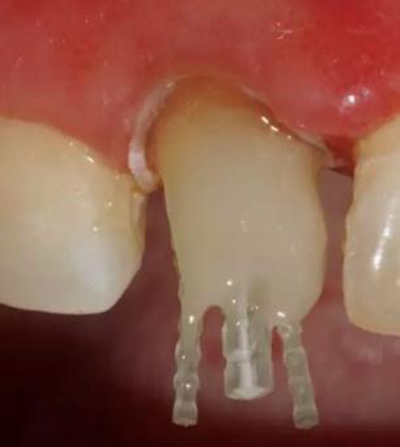

在操作的過(guò)程中要注意無(wú)菌操作,保證纖維樁的無(wú)菌狀態(tài)。推薦將樹(shù)脂核堆好之后再截?cái)嗬w維樁,而不是截?cái)嗪笤僬辰?。如下圖: